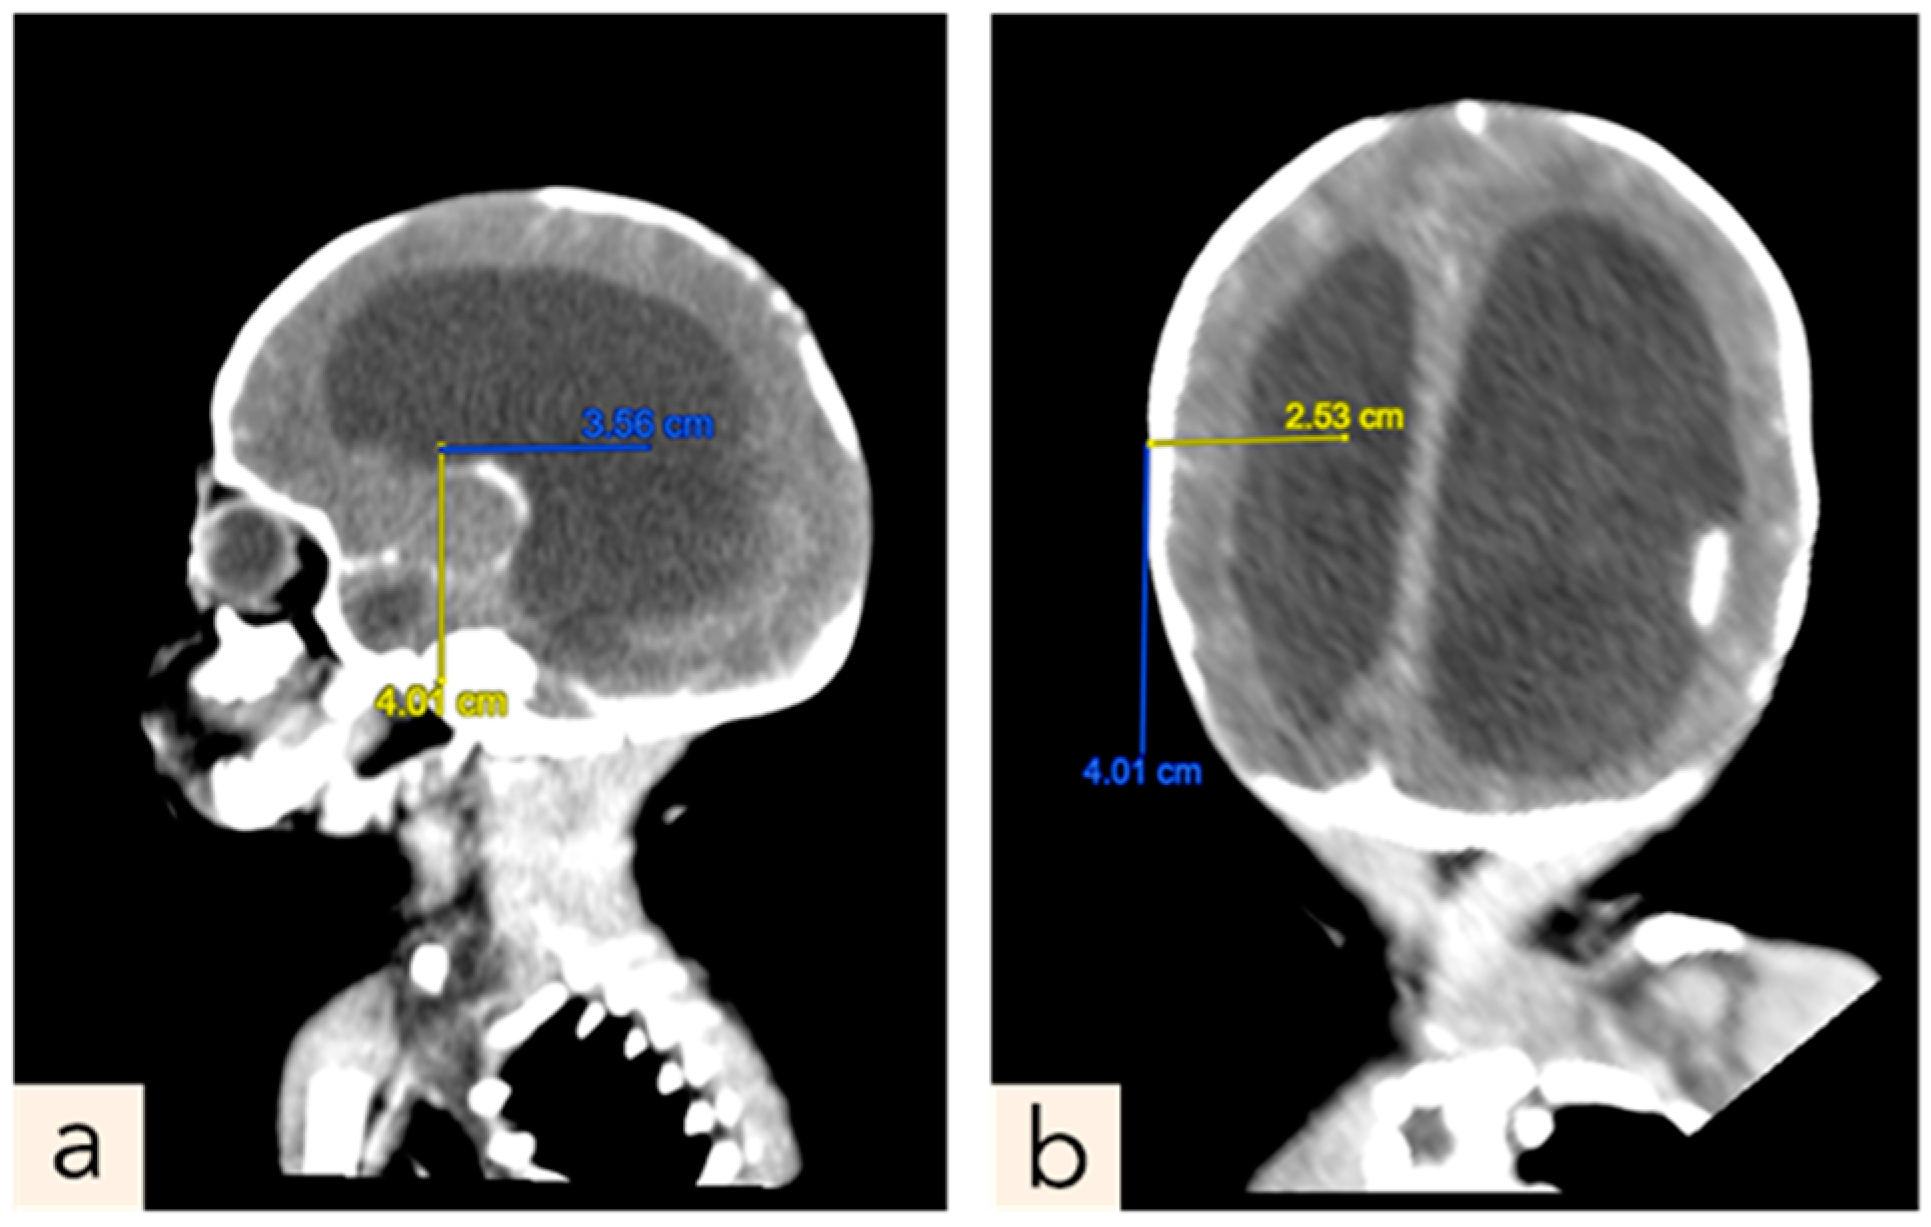

2.1. Patient 1